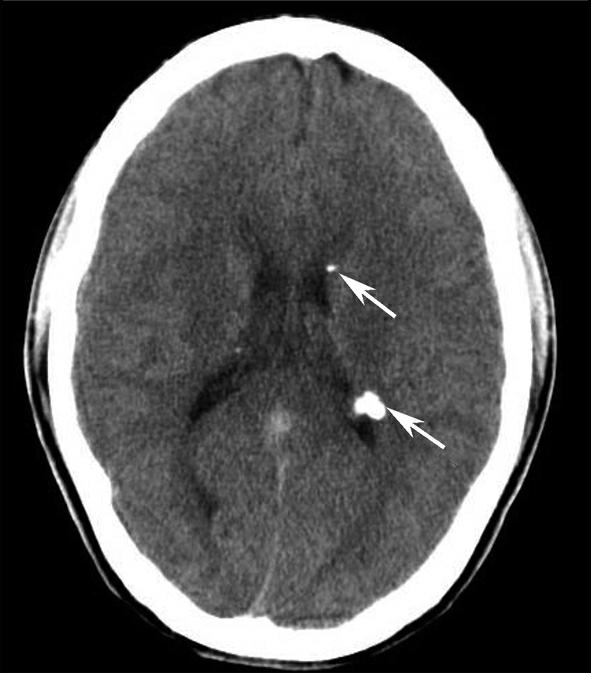

Alberta卒中项目早期CT评分(Alberta stroke program early CT score,ASPECTS)是一种评价急性缺血性卒中患者大脑中动脉供血区早期缺血性改变的简单、可靠、系统化的方法,是常用的脑卒中评定量表之一,可对缺血性病变快速进行半定量评价,有助于判定溶栓效果和远期预后。该评分主要基于CT平扫,具体分区如下(图1-2-76)所示,即选取大脑中动脉供血区2个层面。分区后共10个区域,每个区域记1分。评分时任何区域只要有低密度灶,则扣除该区域得分。正常脑ASPECTS评分为满分(10分),若MCA供血区广泛梗死累及全部区域时,则ASPECTS评分为0分。

图1-2-76 ASPECTS评分脑组织分区

A.在基底节层面(即丘脑和纹状体平面),分为各级分支M 1 、M 2 、M 3 、岛叶(缩写I)、豆状核(缩写L)、尾状核(缩写C)和内囊(缩写IC)后肢等7个区域;B.在基底节以上层面(基底节层面上2cm),包括M 4 、M 5 和M 6 。